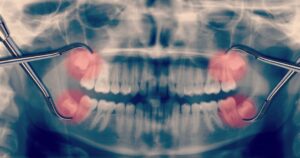

The most definitive way to determine if your wisdom teeth are impacted is through dental X-rays. A dentist can evaluate the position of the teeth and recommend treatment based on their findings. If you experience any of these symptoms or suspect that your wisdom teeth may be impacted, consulting with a dentist for a professional evaluation is essential.

Next, the dentist will carefully extract the impacted wisdom teeth. If the teeth are fully erupted, the procedure may be straightforward. However, if they are impacted beneath the gum line or in the jawbone, incisions may be necessary, and some bone might need to be removed to access the teeth.